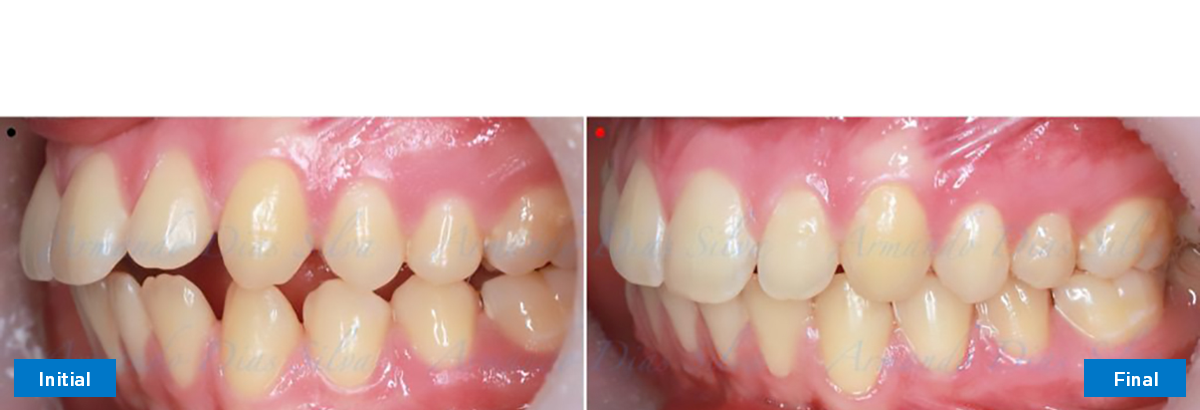

• Molares de clase II

• Incisivos superiores e inferiores proclinados

• Orientación canina desfavorable

• Molares de clase I logrados con distalización y sin elásticos

• Incisivos inferiores retroinclinados, que mejoran la estabilidad a largo plazo

Retención: Arco superior retenido con retenedor transparente. Arco inferior retenido con retenedor lingual unido de canino a canino.